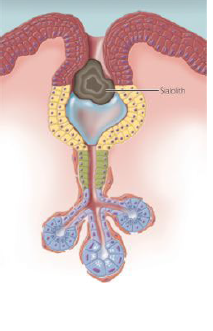

sialolithiasis (salivary stones)

calcified structures, develop within the salivary ductal system

proposed etiology: deposition of calcium salts around a nidus of debris (bacteria, foreign body, epithelial cells, mucous plug, etc)

chronic sialadenitis and partial duct obstruction promotes stone formation

submandibular gland duct as most common location

salivary stones (sialolithiasis) clinical signs

episodic pain or swelling of the affected gland at midline

sialolithiasis (salivary stone) treatment

can sometimes be worked toward the orifice and “passes” by heat, increased fluid intake, and milking/massaging of the gland

lithotripsy (shock waves break up stone into smaller pieces that can be passed)

surgical removal is often indicated

the associated gland may also need to be removed if significant inflammatory damage has occured